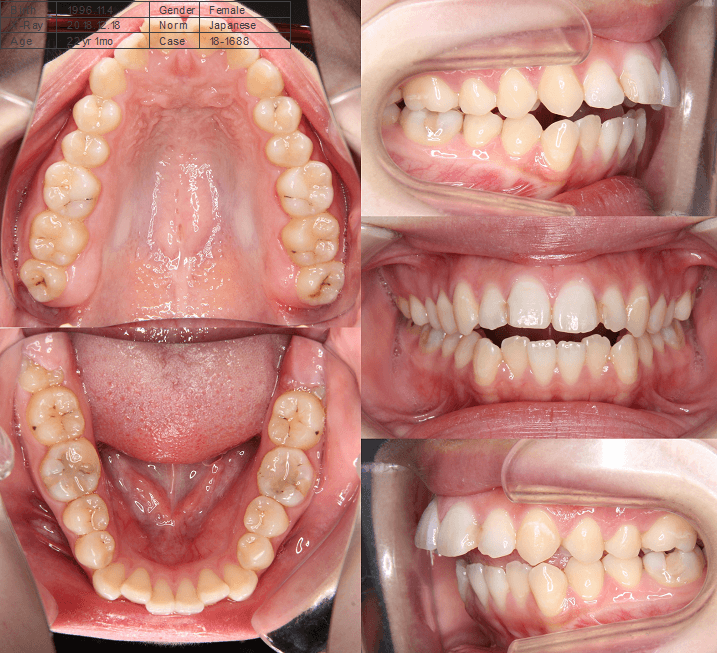

咬み合わせが逆であること(反対咬合)が気になる

| 年齢・性別 | 15歳 女性 |

|---|---|

| 主訴 | 咬み合わせが逆であること(反対咬合)を気にされて来院された女性。見た目や機能面の改善を希望されていました。 |

| 治療期間・回数 | 4年4ヶ月・28回 |

| 費用 | 900,000円 |